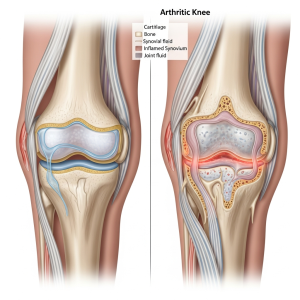

مکانیزم علمی آن چیست؟

آرتروز نتیجه نازک شدن غضروف، التهاب بافتهای اطراف مفصل و تغییر کیفیت مایع مفصلی است.

وقتی غضروف شروع به تخریب میکند:

حساسیت مفصل به بیحرکتی افزایش مییابد

مایع مفصلی غلیظتر میشود

لایههای مفصل اصطکاک بیشتری دارند

حرکت اولیه مفصل سختتر میشود

در نتیجه هنگام بیدار شدن از خواب، مفصل نیاز دارد اول “گرم” شود تا روان شود. این دقیقاً همان خشکی صبحگاهی است.